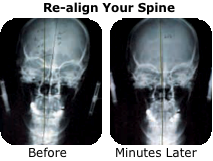

• A new film is taken to verify that your spine has improved

4)  The spinal

5)  A New film is

misalignment is corrected with minimal force.

immediately taken to insure your spine has improved.

Before

After